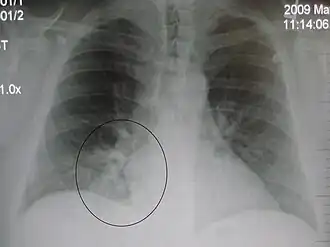

Right upper lobe pneumonia as marked by the circle. -

The discovery of x-rays made it possible to determine the anatomic type of pneumonia without direct examination of the lungs at autopsy and led to the development of a radiological classification. Early investigators distinguished between typical lobar pneumonia and atypical (e.g. Chlamydophila) or viral pneumonia using the location, distribution, and appearance of the opacities they saw on chest x-rays. Certain x-ray findings can be used to help predict the course of illness, although it is not possible to clearly determine the microbiologic cause of a pneumonia with x-rays alone.